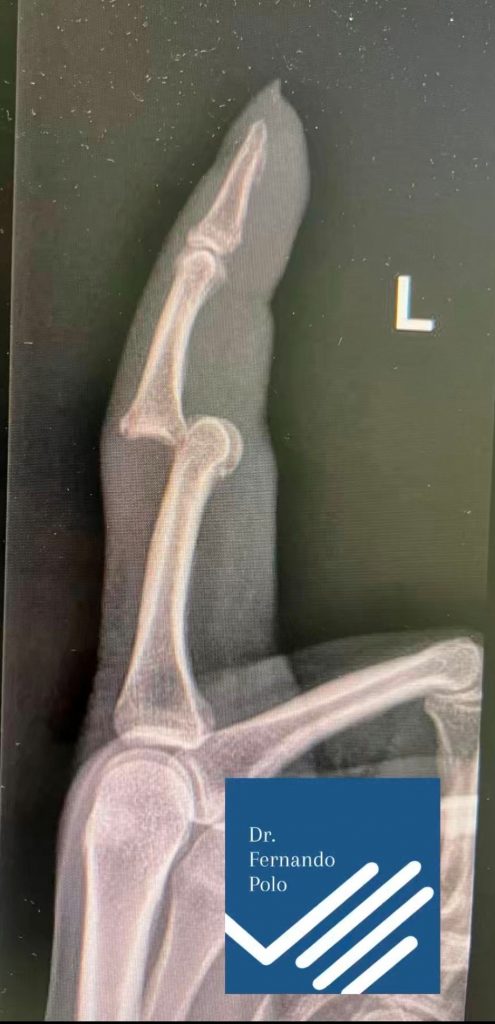

Fracturas de falanges: (Figura 2) Muy habituales. Pueden necesitar inmovilización con férula, aunque algunas se tratan quirúrgicamente si hay desplazamiento.

Figura 2 - Fractura conminuta falange.